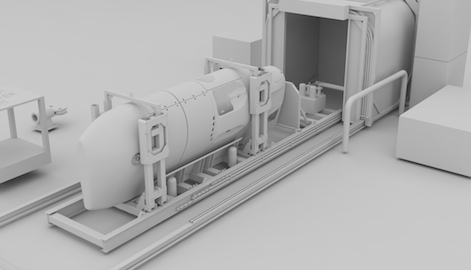

It is vital during total hip replacement surgery that the implant hardware is aligned correctly to limit the possibility of later complications. Every patient has a unique pelvic motion and Optimized Ortho developed dynamic modelling technology which provides pre-surgical information on the patient’s predicted biomechanics.

Optimized Ortho engaged Park Industrial to enable the second stage of their implant positioning system. We created surgical guides uniquely shaped to match the pelvis of each patient that were derived from X-ray and CT scan data. These guides are then fabricated from the latest 3D printing techniques using biocompatible materials.

Park Industrial developed an automated system of guide design that was created using Python scripts and the Solidworks API. This helped to realise the commercial viability of the technology.